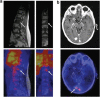

The advent of antibody-based cancer therapeutics has led to the concomitant rise in the development of companion diagnostics for these therapies, particularly nuclear imaging agents. A number of radioisotopes have been employed for antibody-based PET and SPECT imaging, notably ⁶⁴Cu, ¹²⁴I, ¹¹¹In, and (99m)Tc; in recent years, however, the field has increasingly focused on ⁸⁹Zr, a radiometal with near ideal physical and chemical properties for immunoPET imaging. In the review at hand, we seek to provide a comprehensive portrait of the current state of ⁸⁹Zr radiochemical and imaging research, including work into the production and purification of the isotope, the synthesis of new chelators, the development of new bioconjugation strategies, the creation of novel ⁸⁹Zr-based agents for preclinical imaging studies, and the translation of ⁸⁹Zr-labeled radiopharmaceuticals to the clinic. Particular attention will also be dedicated to emerging trends in the field, ⁸⁹Zr-based imaging applications using vectors other than antibodies, the comparative advantages and limitations of ⁸⁹Zr-based imaging compared to that with other isotopes, and areas that would benefit from more extensive investigation. At bottom, it is hoped that this review will provide both the experienced investigator and new scientist with a full and critical overview of this exciting and fast-developing field.